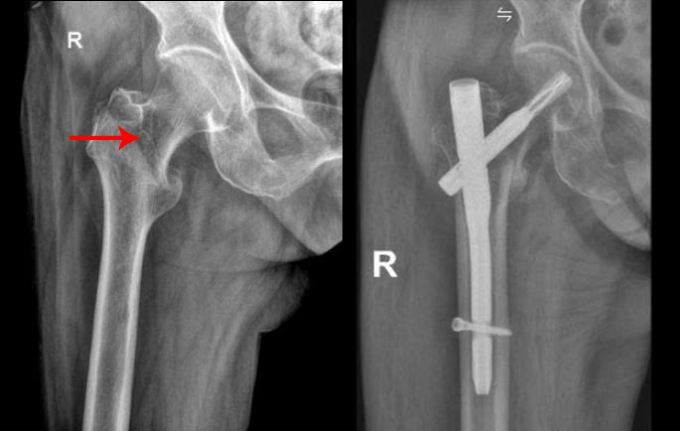

Cụ Lộc, 94 tuổi, ngã đau hông không thể đứng dậy, bác sĩ chẩn đoán gãy liên mấu chuyển xương đùi và phẫu thuật nối lại.

Khám sàng lọc đa chuyên khoa trước mổ cho cụ Lộc, bác sĩ phát hiện một nhánh mạch vành hẹp đến 80-90% và tính toán liều gây mê phù hợp. Êkíp sử dụng bàn mổ chỉnh hình, nắn chỉnh, kiểm tra ổ gãy liên mấu chuyển xương đùi dưới màn hình tăng sáng và hệ thống X-quang di động (C-arm), đưa người bệnh về tư thế mổ thuận lợi nhất nhằm rút ngắn thời gian phẫu thuật.

Trong 40 phút, bác sĩ rạch các đường mổ nhỏ 2-3 cm phía ngoài ổ gãy, đóng đinh nội tủy, bắt vít cố định liên mấu chuyển xương đùi, đóng vết mổ. Phương pháp xâm lấn tối thiểu, giảm nguy cơ trong và sau mổ như mất máu, biến chứng tim mạch cho người bệnh.